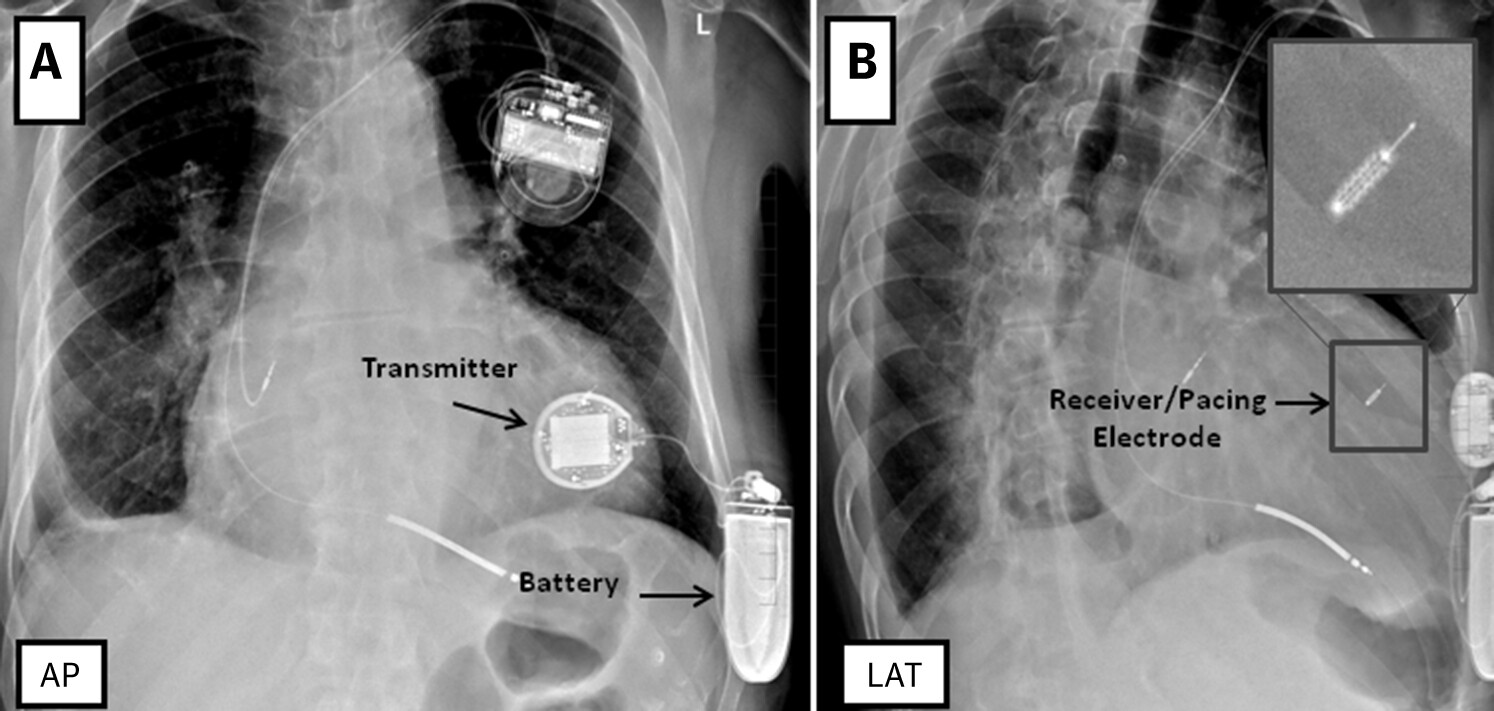

WISE CRT

wiseCRT.jpg

Auricchio A., Delnoy P.P., Butter C., et al. and for the Collaborative Study Group : "Feasibility, safety, and short-term outcome of leadless ultrasound-based endocardial left ventricular resynchronization in heart failure patients: results of the Wireless Stimulation Endocardially for CRT (WiSE-CRT) study". Europace 2014; 16: 681